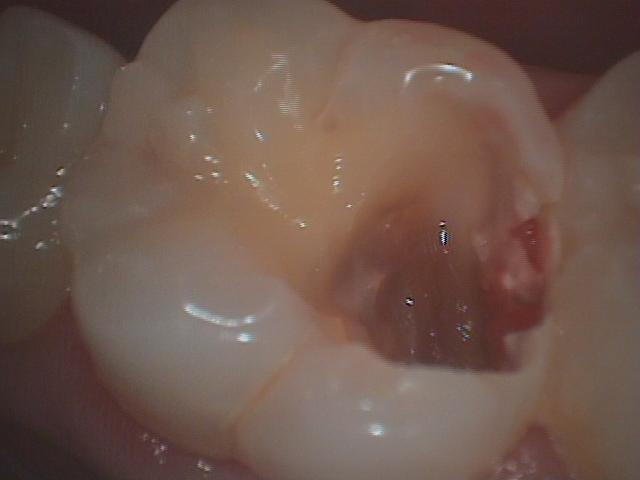

虫歯は中で広がっています

虫歯は中で広がっています | 吉祥寺の歯医者 - さくま歯科 -